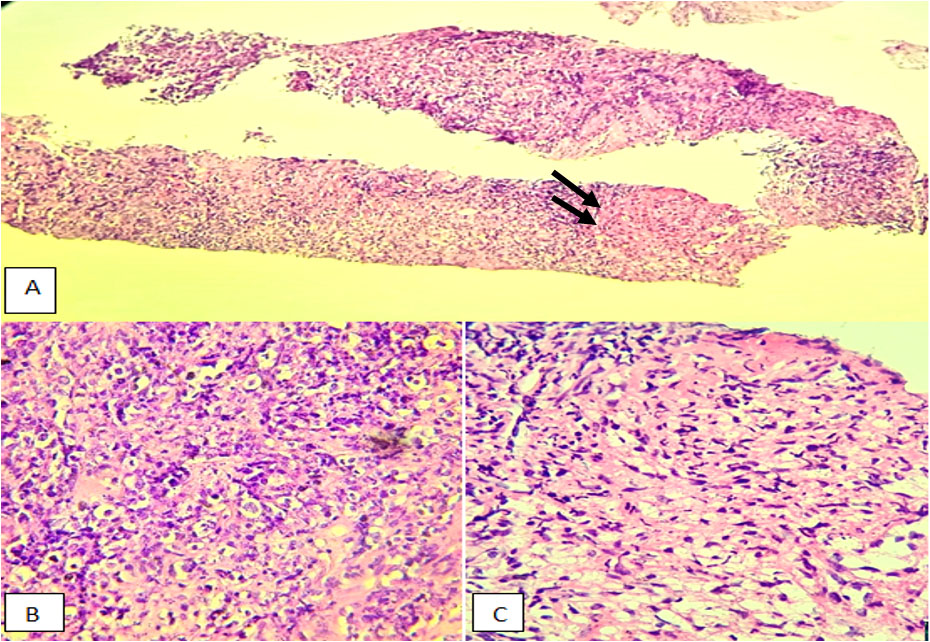

The histological study revealed a diffuse proliferation with a lymphoma-like appearance. The tissue consisted of large, non-cohesive tumor cells exhibiting marked anisokaryosis, vesicular chromatin, and prominent nucleoli. Mitotic figures were evident, and the cytoplasm appeared vacuolated (Figure 2).

Figure 2: Microscopic description: (A) Aggregates of epithelioid histiocytes forming a non-caseating granuloma, surrounded by malignant lymphoid cells (arrows), H&E ×200. (B, C) Higher magnification of malignant lymphoid cells (B) and the non-caseating granuloma (C).